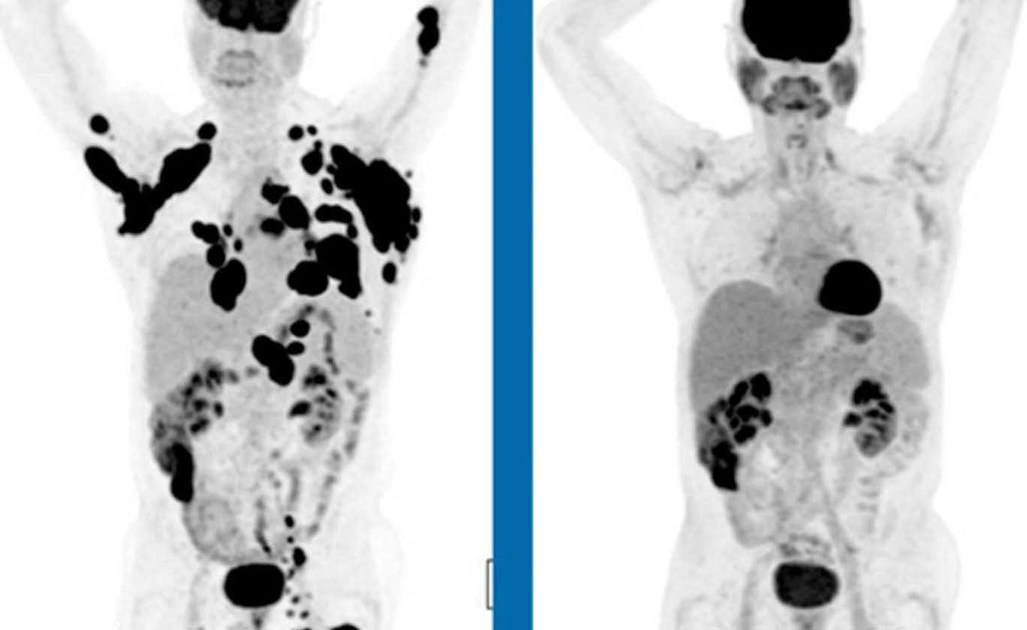

Una compagnia farmaceutica privata ha sviluppato un farmaco sperimentale contro il linfoma che ha prodotto apparentemente risultati “straordinari”, con un terzo dei pazienti molto malati che non mostrano segni di malattia dopo un singolo trattamento.

Quasi 9 mesi più tardi, più di un terzo delle persone trattate non ha mostrato alcun segno della malattia e più della metà era ancora viva.

Nel mese di agosto, però, ha provato la terapia sperimentale CAR-T e, successivamente, vide i suoi tumori “sciogliersi come cubetti di ghiaccio“. Ora è in remissione completa. “Sono stati in grado di salvare la mia vita“, ha detto Padilla.